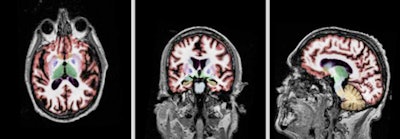

| Sagittal, axial, and coronal plane views (left to right) of a volumetric MRI scan using NeuroQuant on a patient with Alzheimer's. Images courtesy of CorTechs Labs and Dr. James Brewer, PhD, UCSD. |

A commercially available software application (NeuroQuant, CorTechs Labs) is capable of generating automated measurements of brain volume that can be used in conjunction with clinical findings. The software performs automatic labeling, visualization, and volumetric quantification of segmentable brain structures.